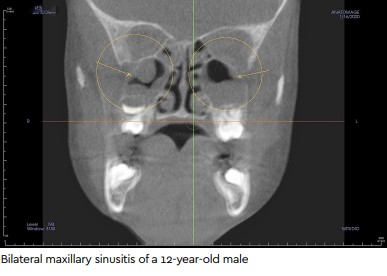

Sunnyvale, TX, where he makes it a point to conduct a thorough examination of teeth and surrounding tissue with the aid of an i-CATTM FLX-V-Series. Here, he explains how and why this CBCT imaging system has transformed his practice and, in many cases, his patients’ lives, ,When I was a young dentist just out of dental school, I joined a practice as an associate dentist, and the plan was for the practice owner to mentor me for 5 years. He would then retire and sell me the practice. For the first 2 months, we would look at x-rays and panos together and talk through cases, but then he went on vacation and left me with an established practice for an entire month. Practicing alone, I quickly realized there was a lot I did not know. Sadly, when he returned, he informed me that his cancer had returned, and he passed away months later., ,I wound up purchasing the practice from his estate, but I was without my mentor, and I needed to learn to walk without my crutch. Soon enough, I realized what I needed to do just that—3D imaging. After learning about the i-CAT, I realized it would not only become my crutch, but also a practice builder. As a young dentist, I wanted to make sure my practice was healthy and growing, and I felt that in order to do that, I would need to see everything with the clarity and detail of cone-beam imaging., ,The i-CAT was a big investment, but it’s been amazing. I haven’t skipped a step and I’ve never looked back. In fact, in the last 6 years, I’ve tripled production in this office, and a lot of that is because of that machine allowing me to do so much more. Not only does it give me the confidence that I can tackle a wide variety of cases, I’m also helping patients solve mysteries on a regular basis., ,Here are a few of the areas where the i-CAT has made a huge difference:,bilateral maxilliar sinusitis of a 12 year old male,In my practice, we choose to take CBCT scans on all new patients, and we’ve started seeing that a lot of people here in Dallas suffer from allergies. In one case, we had a 12-year-old boy with bags under his eyes. He had delayed eruption of his baby teeth, because at 12 he should have most of his permanent teeth in. He’d been undergoing braces treatment. He doesn’t sleep well. He snores. He’s this tall 12-year-old about 5’ 10”, and we’re just trying to figure out: Why aren’t his teeth coming in? What’s happening?, ,So we take a cone beam, and we see that his sinuses are completely full. He is suffering from allergies and has restricted air. He’s always breathing out of his mouth because he cannot breathe out of his nose. So, I refer him to an ENT, who had him undergo 3 months of treatment with steroids and generally flushing out the sinuses. He comes back, we take another CBCT scan, and he’s completely cleared. The bags under his eyes are gone. Now, he’s running cross-country and is the starting quarterback on his high school football team. It’s an unbelievable transformation. Now, he comes in, and he’s about 6’ 2”. I say, “How are you feeling?” He says, “I feel like a new person.”, ,The i-CAT makes it easy to see if a tooth is infected. If there’s a radiolucency at the nerve in the bone, you can see that really well. You can see how many little canals are in each tooth before you do a root canal, and precisely measure how long that tooth is. It allows you to see if there are any cracks within the root. These are things that we cannot do with 2D film., ,When I do a root canal, I go in with full knowledge of the canal and the infection by taking a single scan. I know whether it’s something I can tackle or if a specialist is needed, and that’s a wonderful thing when you’re a clinician on your own., ,I have 2 female patients in their early 60s, and both have beautiful dentition and have had some crown work. They come in every 6 months, and they were both having issues around the same time—TMJ, headaches—so they went to their primary doctor, who then sent them to a specialist. Ultimately, they wound up in a neurosurgeon’s office, still trying to figure out what was going on., ,When they came to my office for their routine cleanings, we did a medical history breakdown and learned what was going on. So, I decide to take CBCT scan and look closely at their back molars, because I had a strong suspicion that the problem would have something to do with the teeth. Sure enough, both of them had infected upper-right back molars—just on one of the roots. We could see it plain as day, although you would not be able to see it on a 2D x-ray image. I sent them for root canal treatment. They already had crowns on these teeth, and the endodontist went straight through the crowns, and all their pain went away. They had been spending money on various doctor visits and were about to be placed on medication, but it all had to do with a sick tooth—clearly visible on the CBCT scan., ,With pediatric patients, I’m able to take a quick, low-dose CBCT scan when medically necessary and easily decide with the parents about whether the wisdom teeth need to come out. In general, one of the best things I do for my patients—especially the younger ones—is look at that scan and explain the things that we are looking for, whether it’s delayed permanent teeth, crowding, breathing issues, or something else., ,After taking a quick scan, I’m able to have a very thorough conversation with their parents about their child, who may be having sleeping problems, snoring, having issues at school, or getting sick frequently or experiencing allergies. I always think, “There may be more to this.” And the scan answers that question. I can then refer them back to their pediatrician, to an ENT for allergies, or whomever is needed based on what we detect., ,One thing that’s really nice about the i-CAT is you are able to take a scan and use the software to digitally plan whether this implant can fit in a given space. You can measure all different ways and check different anatomy as far as sinuses. You can check the density of the bone to know that the implant is going to be in a solid position, which is important because everybody’s bone is different., ,I use the i-CAT for guided surgery. We send out the scan and an impression so a guide can be 3D printed, which allows me to place implants with amazing accuracy., ,Gum disease is very prevalent in our community. By taking a scan, you can really see in 3D how much bone loss a patient might have around a tooth. We blow up the image and show it to them on the big screen. It is quite a visual for the patient and much more helpful than us trying to talk to the patient in terms that we understand but they do not. The cone-beam scan is an amazing tool for patients’ case acceptance., ,Because our practice sees the value of capturing CBCT scans when necessary, my team is trained on how to speak with patients and help them understand the reason for taking the image. They show the patients what we’re looking for—growth and development, sinuses, airway, alignment, and so many other things. If we see something out of the ordinary, we refer them to a specialist or I’ll take care of it myself, but this has become a very important part of what we do and has made an impact both on patients’ lives an the growth of our business.,i-cat flx v-series